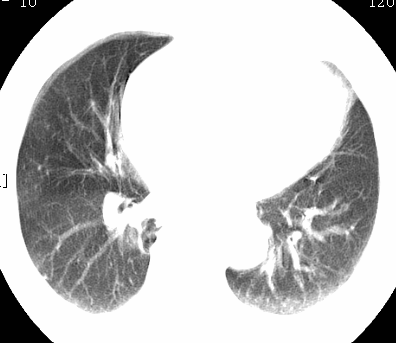

标题: CT26680:肺部右下肺静脉干结节的界定 [打印本页]

标题: CT26680:肺部右下肺静脉干结节的界定

经追查说有支扩咯血病史,但不确定

考虑1、周围型肺癌,2肺静脉畸形,前者可能大,建议增强检查。

考虑1、周围型肺癌,2肺静脉畸形,前者可能大,建议增强检查。支持!

不排除右肺下叶周围型肺癌可能。

中心型肺癌,纤支镜可帮助明确。